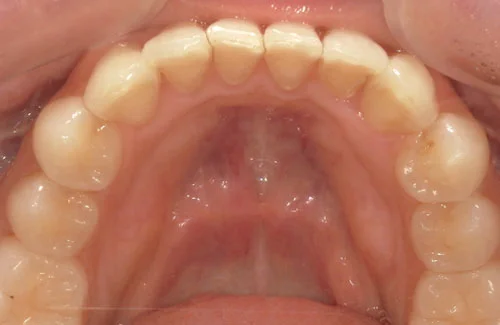

治療前後の写真

<症例2>歯が全体的にガタガタ、出っ歯でお悩み

歯列のアーチがやや狭く、それにより上下の前歯部にガタつきが生じている状態でした。

小臼歯部をわずかに広げてスペースを作ることで、お口元を整えつつガタつきを改善しています。

患者様と症状

主訴:全体的なガタガタ、出っ歯

性別・年齢:30代女性

問題点:上下前歯部の叢生(中程度)、ディープバイト

診断:前歯部の叢生を伴うアングルⅠ級の不正咬合

主なリスク:矯正中一時的に咬合しにくくなる、歯肉退縮

症状:叢生(そうせい) 過蓋咬合(かがいこうごう)

治療内容

治療期間:9ヶ月

治療費用:660,000円(税込)

プラン:26枚コース/モデレートプラン

抜歯:親知らずのみ抜歯

再診治療費:無し

追加治療費:無し

保定装置費:無し